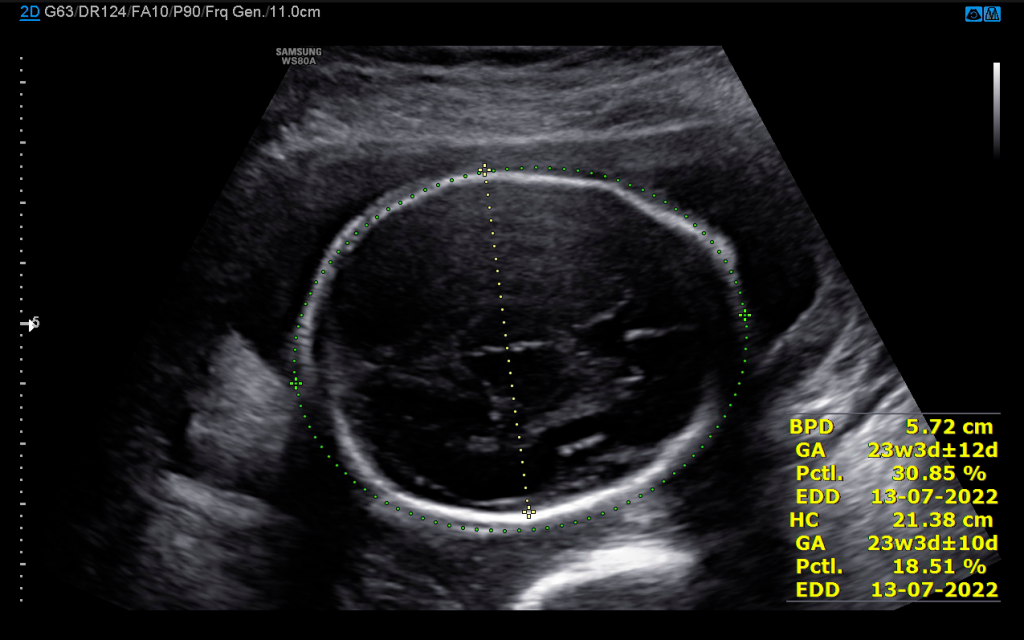

Idade gestacional pelo ultrassom é confiável?

Dúvidas, Gestantes

20/03/2022   1244 Views

Quando uma mulher descobre que está grávida, uma das primeiras coisas que ela quer saber é de quanto tempo está…